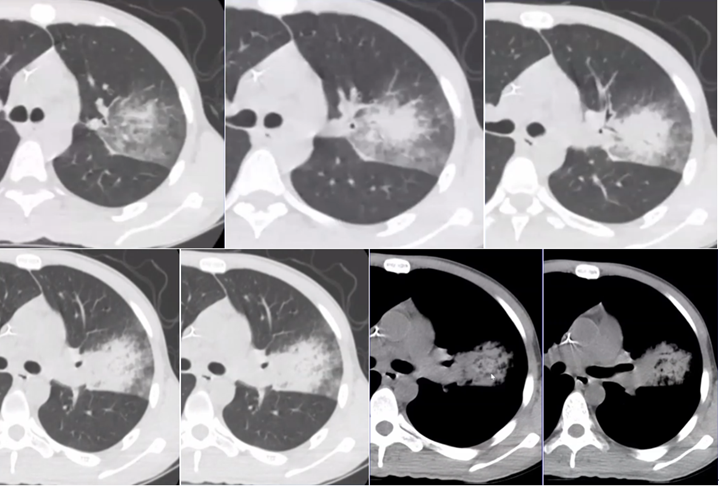

曲霉的破坏程度与曲霉菌丝生长相对成比例,其破坏范围形成的坏死、空洞及分隔均少于毛霉,而毛霉的破坏力更强。下图是一个结节,周边有晕征,说明病变是血管侵袭性,其中有很多小气泡,没有液平面,说明有菌丝的存在,菌丝固定了坏死物。但纵隔窗看到分隔特别粗大,小气泡特别大,说明坏死占的比例更多,坏死程度更严重,而菌丝的生长与坏死程度不成比例,所以是“坏死多菌丝少”,这是毛霉的特征。而曲霉感染则是“坏死多菌丝多”,坏死物相对固定,小气泡并未形成大的空洞。这也是曲霉和毛霉重要的鉴别点(图22)

图片

图22  毛霉和曲霉感染坏死、空洞的区别

注:A、B为毛霉所致病变,空洞内分隔粗大不均,空洞更大;C为曲霉所致坏死物固定,小气泡多。